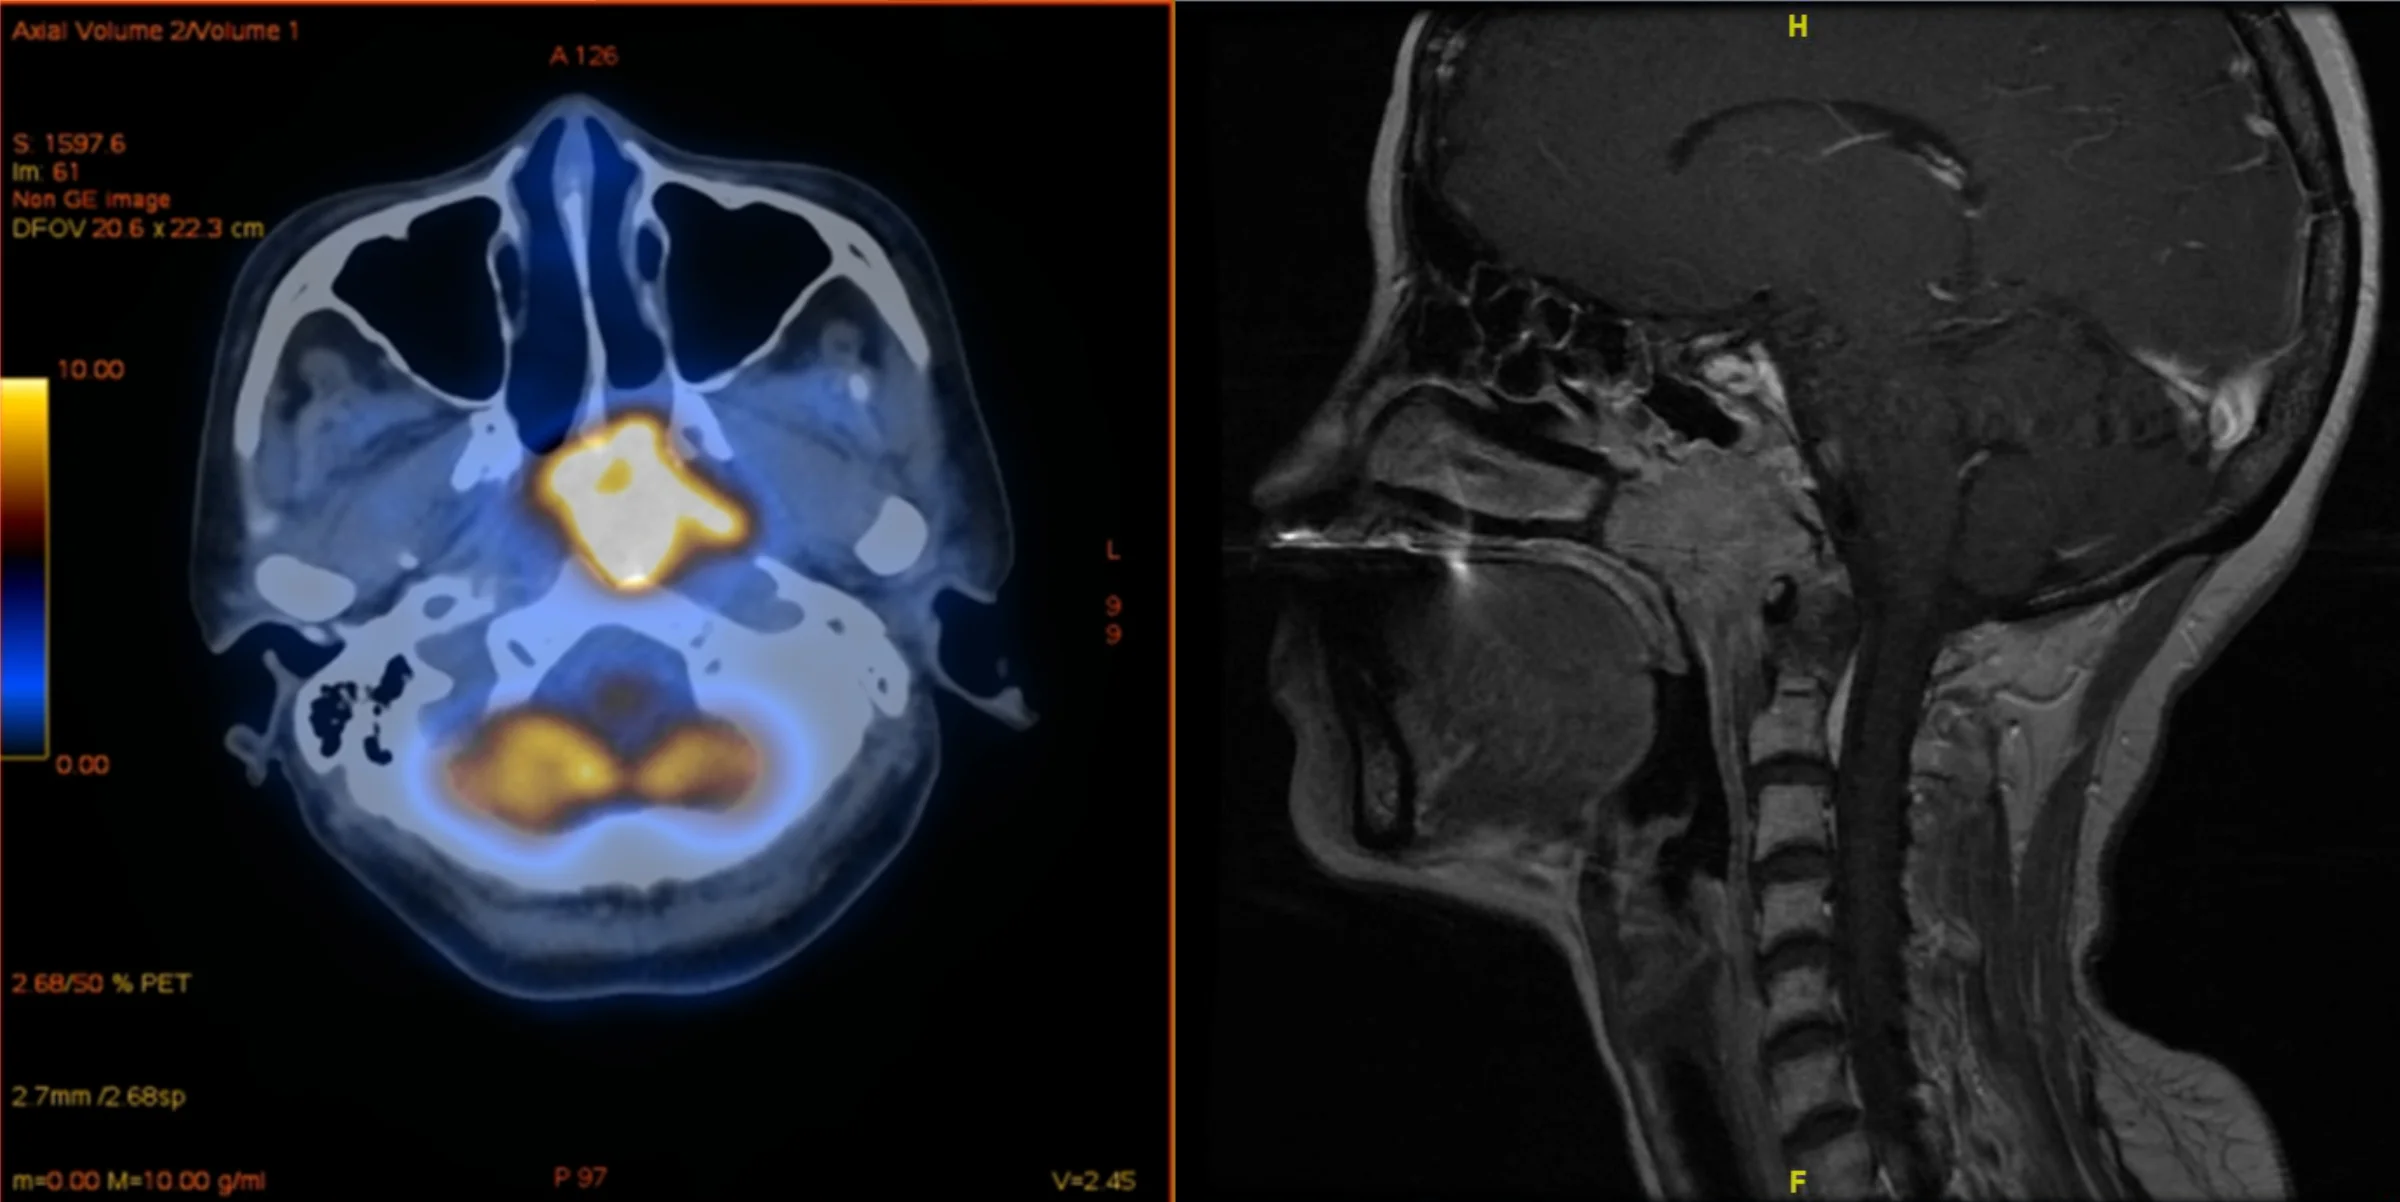

Nasenrachentumore (gelb markiert)

sind in Ländern Südostasiens eine häufige Erkrankung. Die Sorge, die Therapie könne ungünstig mit einer Covid-Impfung interferieren, ist aber wohl unbegründet.